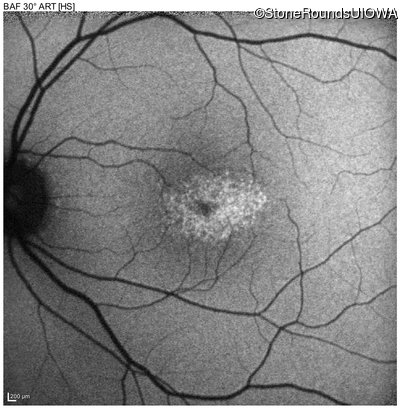

Optical Coherence Tomography - Right - 20/16 sc

Exemplar / OCT Stack